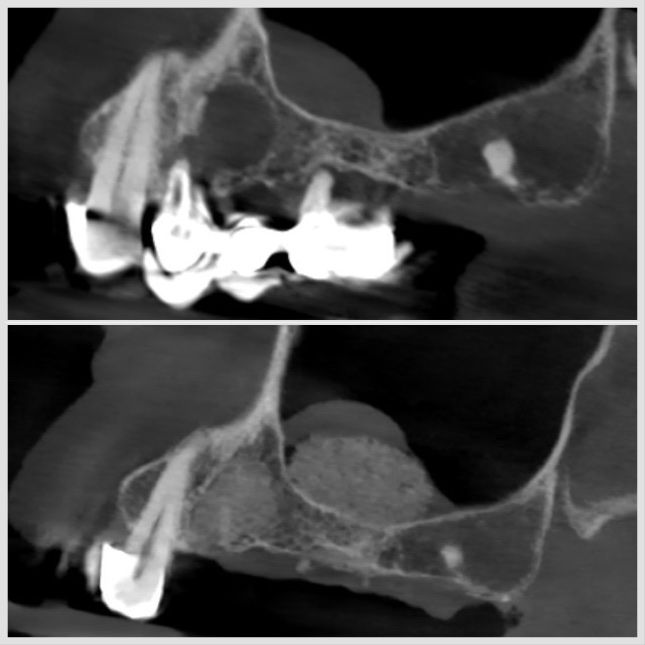

Sinus lift associé à une régénération osseuse guidée (ROG) pour reconstruction maxillaire à Apolline Dental Care à Corbeil-Essonnes

Sinus Lift

#chirurgie

Sinus lift réalisé avec planification 3D pour préparer la pose d’implants dans la zone maxillaire à Apolline Dental Care

Sinus lift avec comblement osseux réalisé dans la zone maxillaire pour placement d’implant à Apolline Dental Care à Corbeil-Essonnes